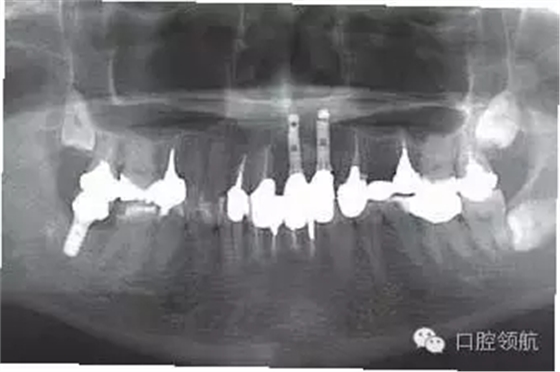

上述的患者具有較高的笑線,所以不影響美學(xué)效果(圖4、圖5)。近年,適合于牙齦色的瓷粉和聚合樹(shù)脂應(yīng)用于臨床,是較為可行的應(yīng)對(duì)方法。

圖4 上部修復(fù)體戴入口內(nèi)后,牙列和口唇的關(guān)系,由于笑線較高的原因沒(méi)有影響美學(xué)效果。

圖5 上部修復(fù)完成后的全景X線片。